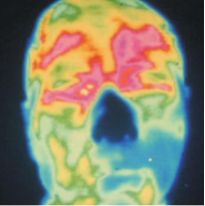

△脸部热像图显示前额右侧和眼睛(图像左侧)异常凉区。这种热信号暗示动脉畸形或动脉变窄或变硬,这表明可能发生中风。